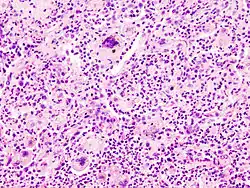

- TOUTON-Riesenzelle - Schaumzellen, bei denen um eine kleine schaumfreie Insel mehrere Kerne ringförmig angeordnet sind, Vorkommen z.B. bei juveniler Xanthogranulomatose, siehe Abb.